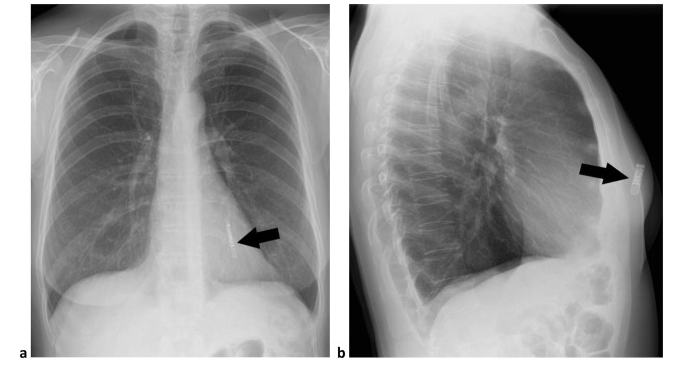

이식형 심장 사건 기록기 (Implantable loop recorder)

이식형 심장 사건 기록기 (ILR) 은 USB 메모리 스틱과 비슷한 납작한 모양의 작은 물체입니다. single-lead 심전도를 기록, 저장할 수 있는 기능을 가지고 있습니다. (최대 3년) 특정 서맥, 빈맥 부정맥이 발생할 경우 자동으로 심전도를 저장할 수 있습니다. 환자가 증상이 있을 때 추가적으로 심전도를 기록할 수 있습니다.

가장 작은 ILR 인 Reveal LINQ 는 4.48 cm x 0.72 cm 크기입니다.